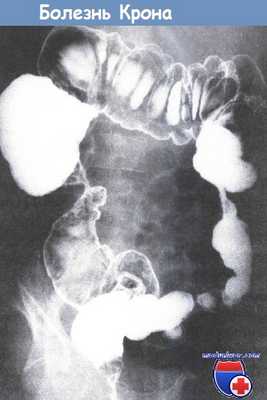

• Исследование тонкой кишки: пассаж контраста по тонкой кишке, КТ энтерография или капсульная эндоскопия (внимание: наличие стриктур!).

• Рентгеноконтрастные исследования (ирригоскопия с барием или гастрографином): состояние слизистой, конфигурация кишечника, стриктуры, трещины и свищи; исследование противопоказано у больных с острым заболеванием (может усугубить ситуацию при токсической дилатации).